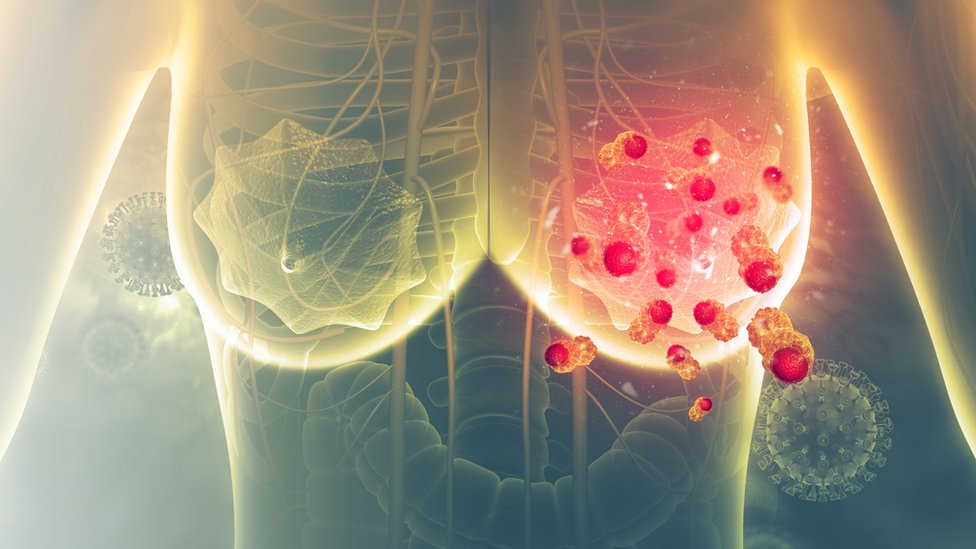

El de pecho es el cáncer más frecuente en las mujeres y afecta globalmente a 2,1 millones de mujeres por año, según la OMS. Crédito: Getty Images

El cáncer de pecho es el cáncer más frecuente en las mujeres, y afecta a 2,1 millones de mujeres al año en todo el mundo, según la Organización Mundial de la Salud.